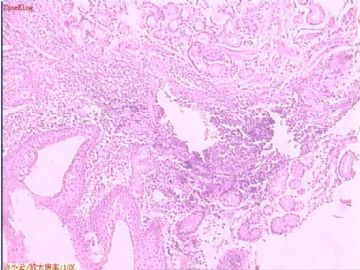

贲门息肉?

姓    名: ××× 性别:  女 年龄:  53

简要病史:  胃镜见,食道下段齿状线上可见一圆形隆起,有蒂,表面光滑,大小0.5X0.5X0.3cm.

各位老师,胃粘膜处出现的鳞状上皮有问题么?

• 贲门息肉?图2

图2

正好是齿状线腺鳞交界处粘膜

鳞状上皮没大问题,可能受炎症影响,稍有增生.

没有发现恶性证据,小心点儿可以拖个尾巴,譬如伴轻度异型增生。

本帖最后由 于 2009-11-21 09:51:00 编辑   谢谢各位老师指点,最终诊断为:贲门慢性炎症,伴局灶细胞轻度异型增生。